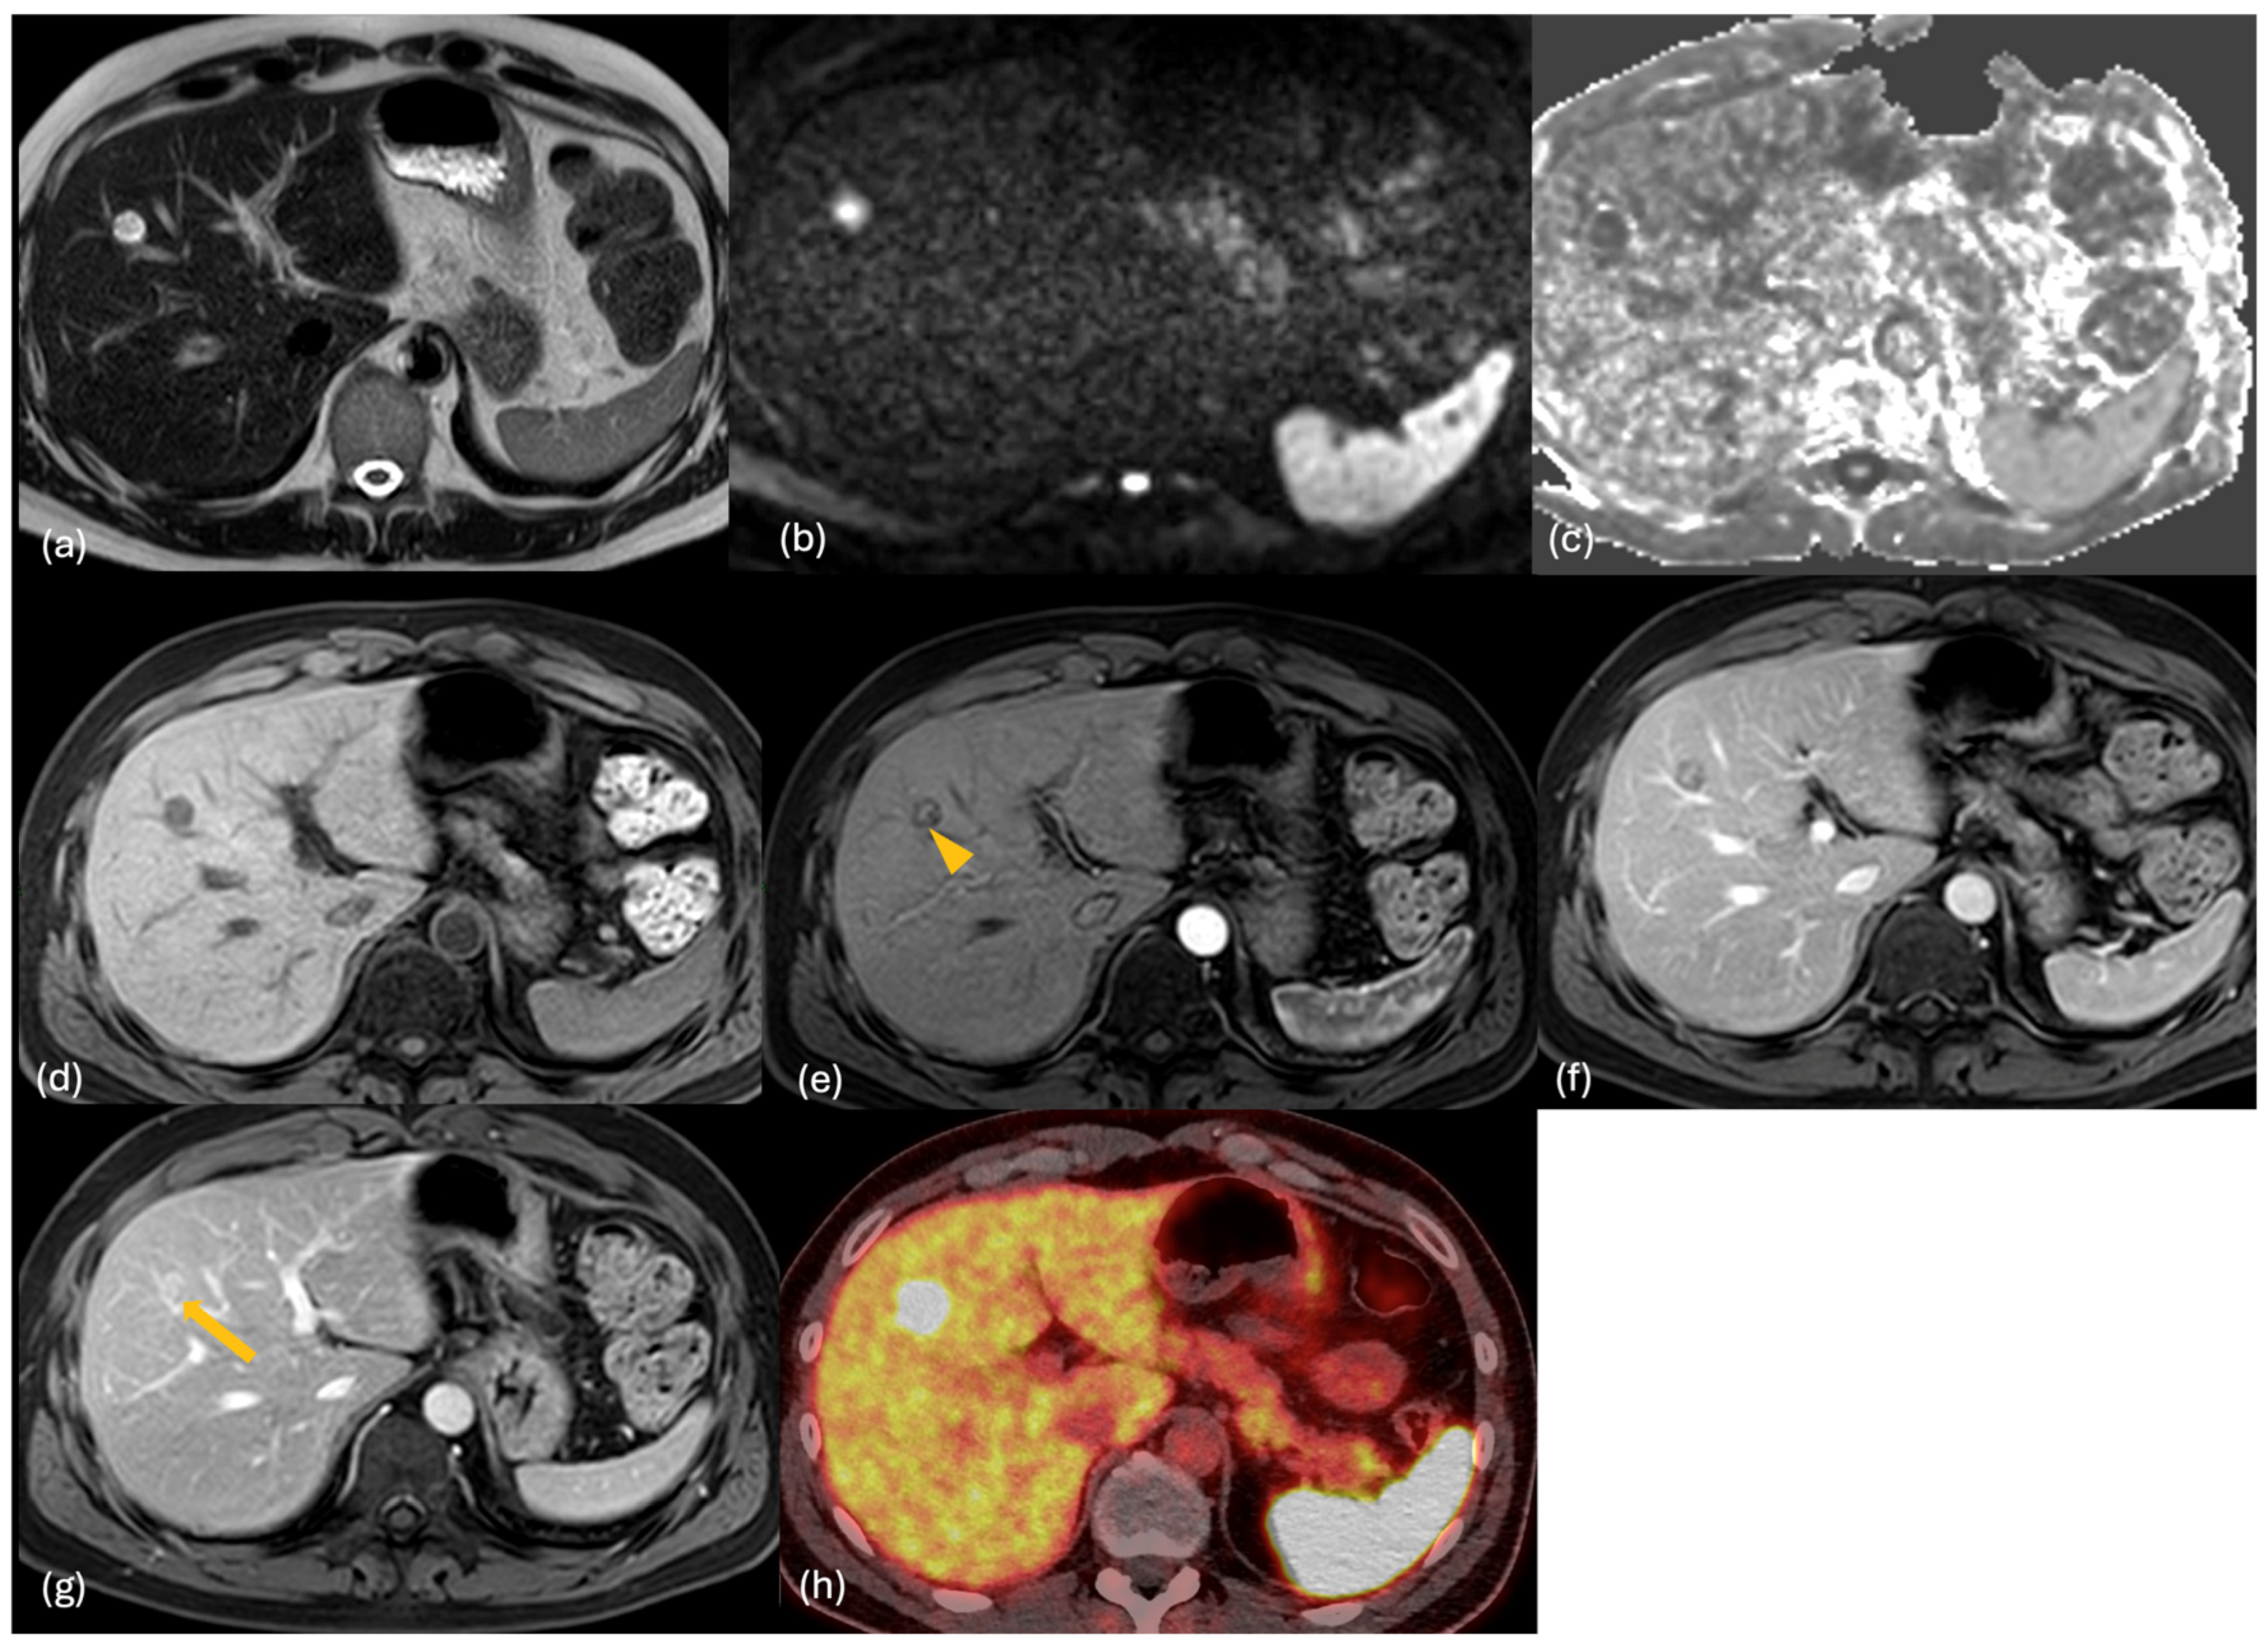

2.3. MRI

2.4. PET-CT